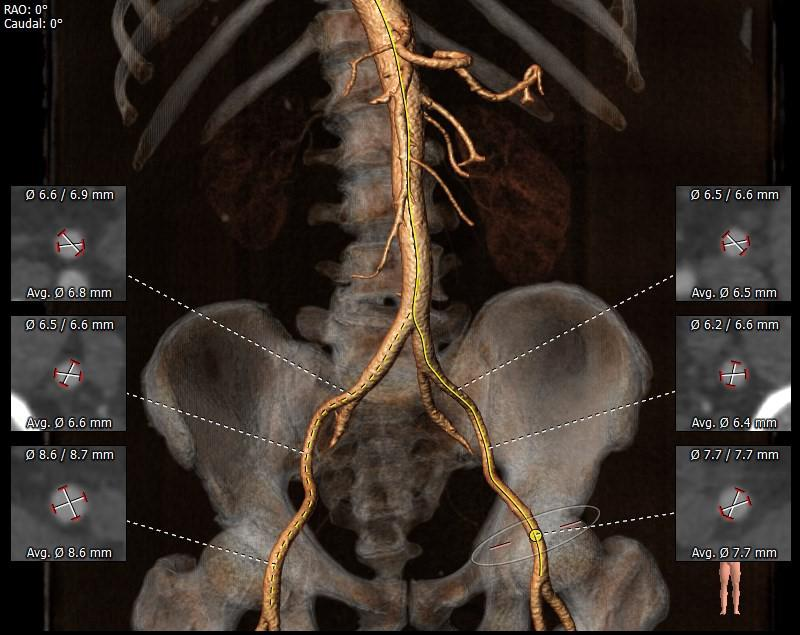

主动脉根部评估

外周分析

• 该患者外周血管内径,走形良好,无附壁钙化,预计采用右股为主入路,左股为辅入路。